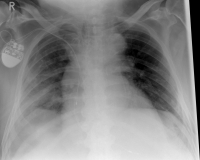

The rib fracture is a common injury to the chest. It occurs frequently in (car) accidents, falls during cycling and contact sports. Due to their anatomical position, especially the 4th - 9th ribs are affected.

If three or more ribs are broken on the same side, this is called a flail chest. A rib fractured in more than one place is called a piece break.

In the case of a rib fracture, patients often experience breath-related pain, which increases especially with deep inhalation. Likewise, coughing or pressing on the affected area can be painful. Bruising on the outside (hematoma) and swelling may be visible. In rib serial fractures, there may also be the presence of an unstable thorax, which manifests itself as paradoxical breathing. That means, the opposite movement of the thorax during respiration occurs, during which the thorax contracts during inhalation and bulges outward during exhalation.

As a rule, the rib fracture is diagnosed by X-ray. In severe cases or ambiguous X-ray findings, a layer imaging, for example computer tomography (CT), can also be performed.

Rippenserie re                   Rippenserie re1